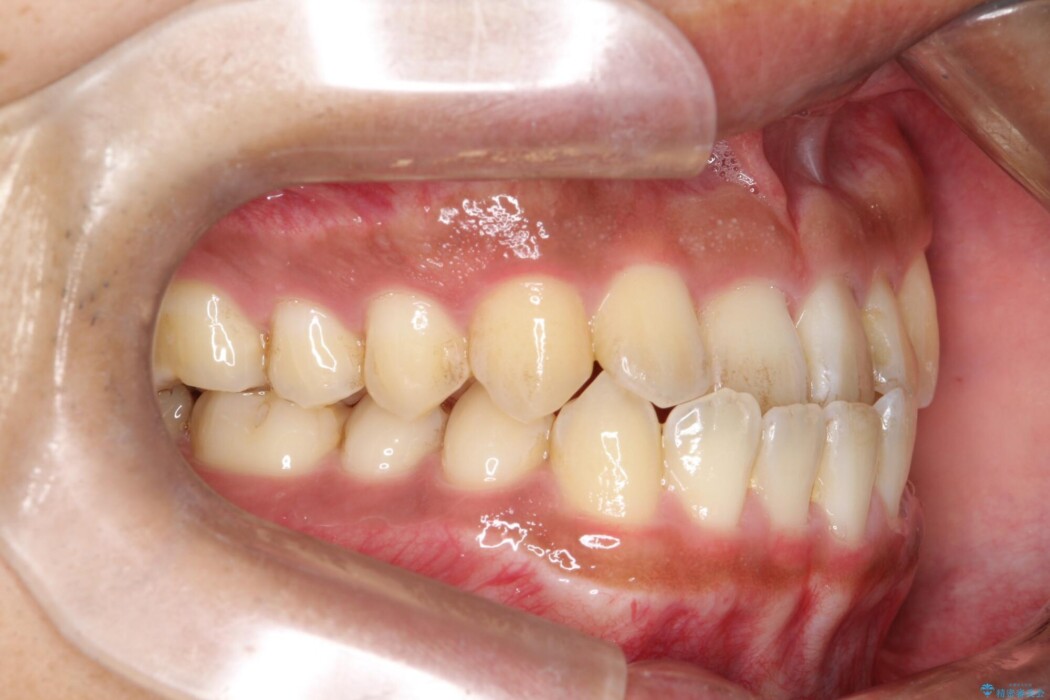

下の前歯が上の前歯より前にあるため、かみ合わせが悪く改善したいとの主訴で来院されました。

受け口とも呼ばれる反対咬合のため、下顎にIPRを加えスペースをつくり矯正をすることによって、前歯の正常被蓋を得ることができました。